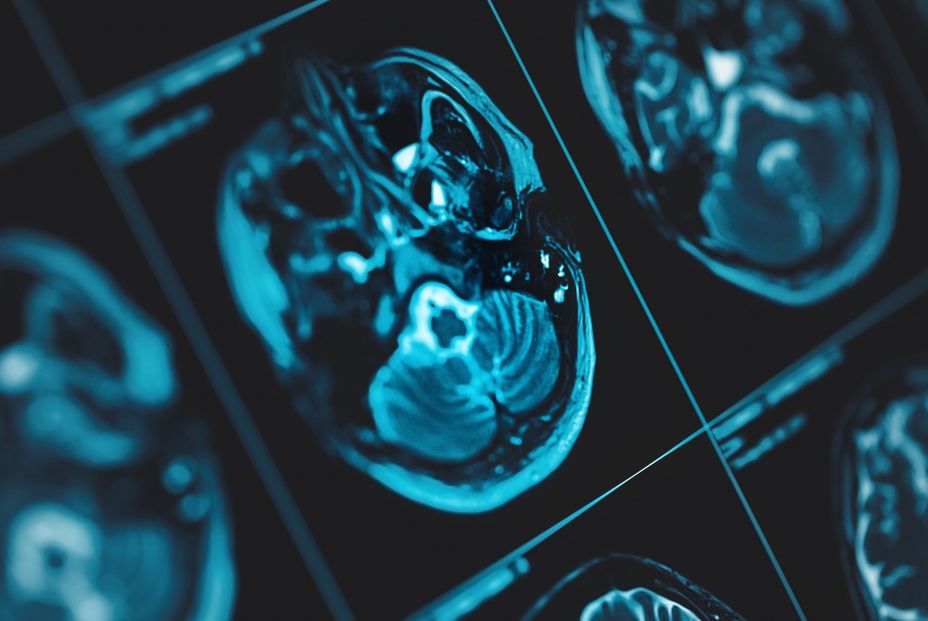

La personas que tienen periodontitis pueden tener el triple de riesgo de padecer ictus isquémico y el doble de padecer demencia de tipo alzhéimer, además, se considera que diferentes intervenciones de salud oral pueden reducir el riesgo de sufrir estos desórdenes neurológicos, según revela el informe de consenso llevado a cabo por el grupo de trabajo conjunto de la Sociedad Española de Periodoncia y Osteointegración (SEPA) y la Sociedad Española de Neurología (SEN).

Este informe, presentado en rueda de prensa este jueves, muestra la asociación existente entre la periodontitis y la enfermedad cerebrovascular (ECV) y entre la periodontitis y la demencia. La vicepresidenta de SEPA, la doctora Paula Matesanz, ha señalado que "el resultado del informe muestra que la periodontitis aumenta el riesgo de padecer ictus isquémico y demencia de tipo alzhéimer".

Los datos epidemiológicos extraídos del informe revelan que las personas con periodontitis tienen 1,7 veces más riesgo de padecer demencia tipo alzhéimer y 2,8 veces más riesgo de sufrir un ictus isquémico que las personas periodontalmente sanas.